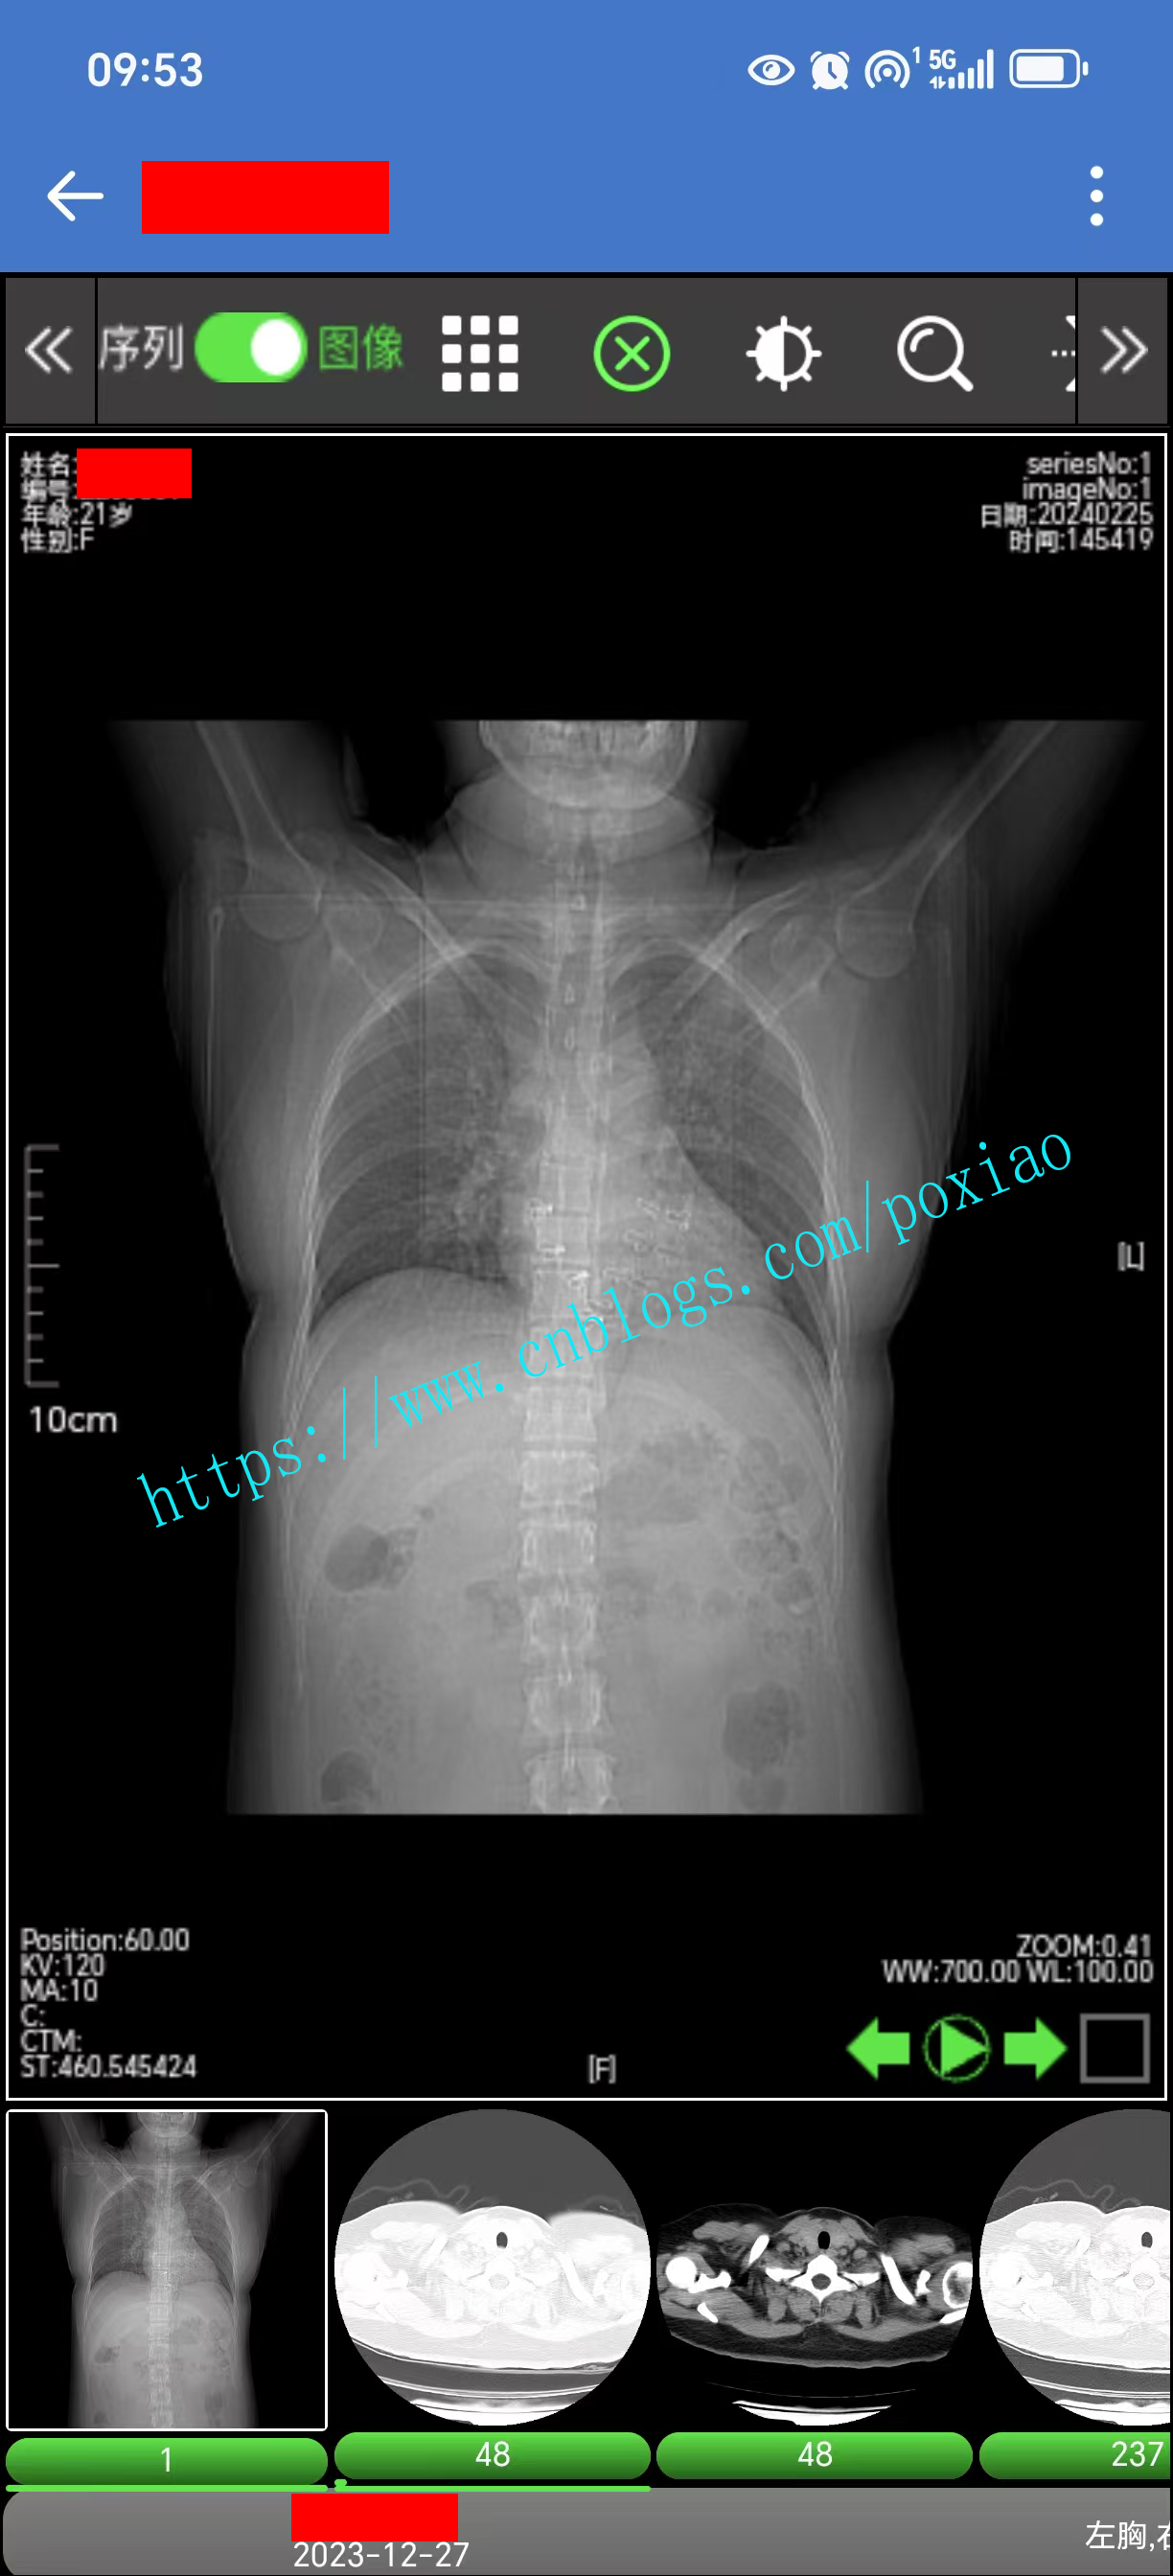

1.支持电脑、手机、平板等设备,支持HarmonyOS、IOS、android、window、linux、信创、麒麟等主流操作系统,支持电子胶片,可在任意终端任意系统的H5浏览器上调阅医学影像。